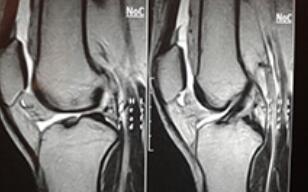

入院后,王怀庆主任马上为小吴安排了检查,症状:手关节肿胀、疼痛,早上有6分钟晨僵,膝关节肿胀,下蹲困难,行走时疼痛。X光检查结果:双膝关节未见脱位,关节间隙狭窄,关节面光滑,关节囊肿胀。化验:AS...[详细]

王怀庆主任为刘先生做了详细的检查。在经过认真查体后发现,刘先生双手指远端指间关节海伯登结节,关节僵硬,握拳无力。双膝肿胀Ⅲ°,皮温高,浮髌试验(+),屈100°伸-20°。...[详细]